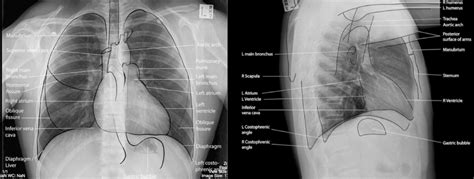

- RTG vyšetrenie hrudníka